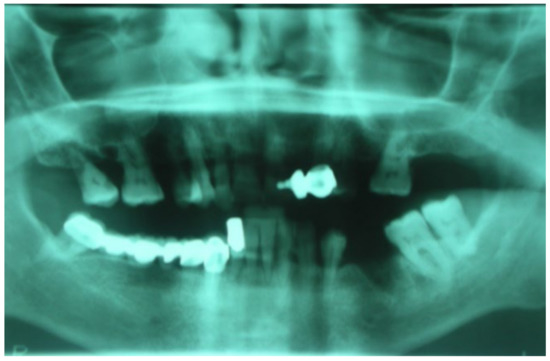

3.1. Clinical Case 1